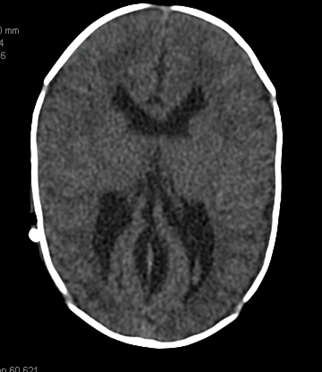

TC/ressonância nuclear magnética (RNM) de crânio: deve ser realizada se houver suspeita de hipertensão intracraniana, principalmente se os sintomas forem acompanhados por cefaleia intensa. Em neonatos e bebês pequenos, é preferível a ultrassonografia.[Figure caption and citation for the preceding image starts]: Tomografia computadorizada (TC) mostrando volume aumentado dos ventrículos laterais secundário a hidrocefalia não comunicanteDos acervos do Dr. R.A. Gomez-Suarez e Dr. J.E. Fortunato; usado com permissão [Citation ends].